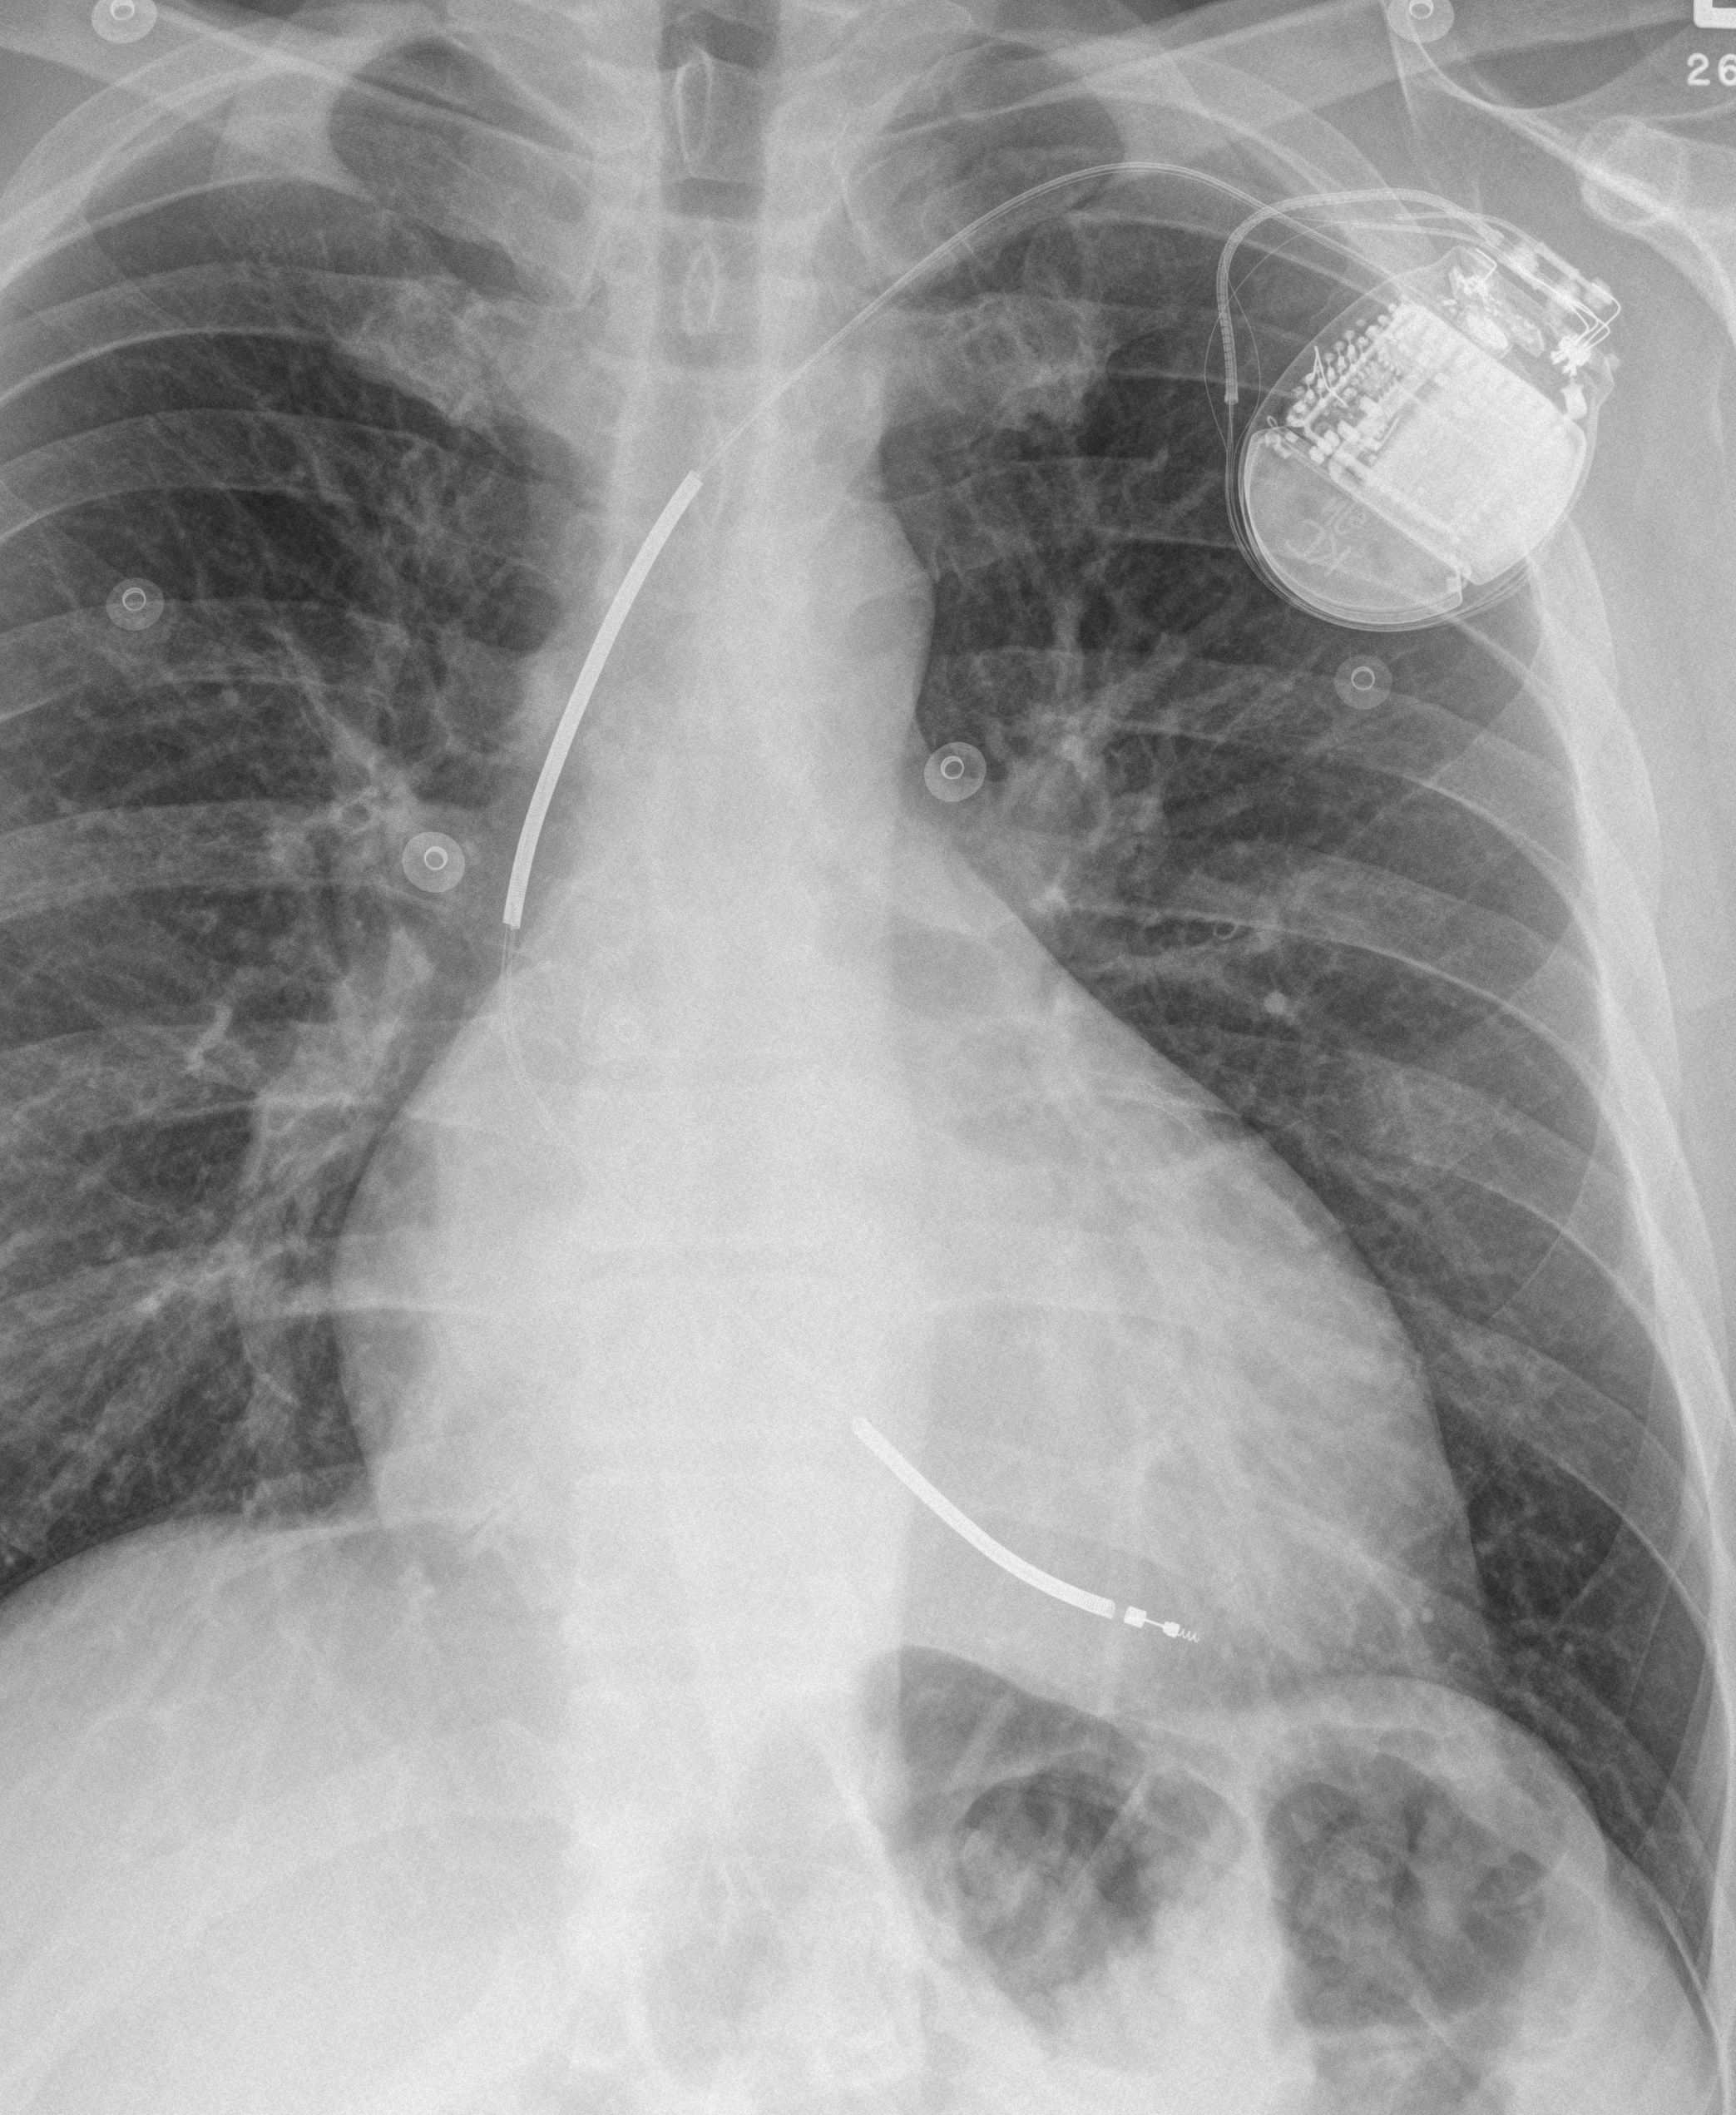

ICD PA